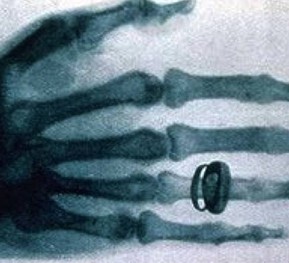

X光機(jī)主要是由X光機(jī)電源,X光球管以及控制電路等組成,是產(chǎn)生X光的設(shè)備,目前已廣泛應(yīng)用于醫(yī)院協(xié)助醫(yī)生診斷疾病,工業(yè)的無損探傷,科學(xué)教育,機(jī)場和火車站的安全檢查等

圖像監(jiān)控法是直接從x射線透視圖像構(gòu)形來判斷物品的,因此,被檢物是否可疑,取決于監(jiān)視器或顯示器上的圖像。顯示器或監(jiān)視器上出現(xiàn)的不常見物或異形物,都應(yīng)視為可疑物品。那些不能準(zhǔn)確辨認(rèn)的物品也應(yīng)視為可疑物品,需仔細(xì)觀察,根據(jù)需要可將圖像定位分析。